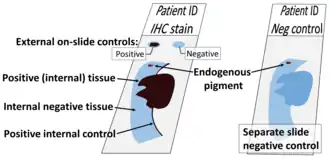

Methods to eliminate background staining include dilution of the primary or secondary antibodies, changing the time or temperature of incubation, and using a different detection system or different primary antibody. Quality control should as a minimum include a tissue known to express the antigen as a positive control and negative controls of tissue known not to express the antigen, as well as the test tissue probed in the same way with omission of the primary antibody (or better, absorption of the primary antibody).[5] [18]

- ↑ Image by Mikael Häggström, MD. Reference: Torlakovic EE, Francis G, Garratt J, Gilks B, Hyjek E, Ibrahim M, et al. (2014). "Standardization of negative controls in diagnostic immunohistochemistry: recommendations from the international ad hoc expert panel". Appl Immunohistochem Mol Morphol. 22 (4): 241–52. doi:10.1097/PAI.0000000000000069. PMC 4206554. PMID 24714041.